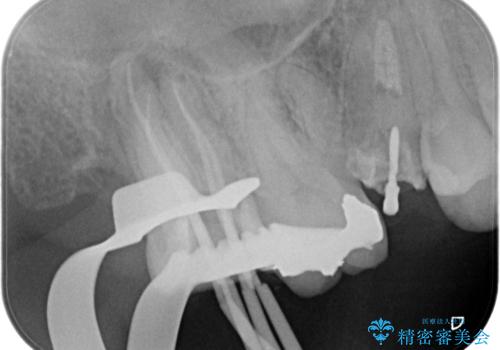

今回の精密根管治療では、まず治療中に唾液や細菌が入らないようラバーダムで患部を隔離しました。次に、肉眼では見えない根管内部を歯科用顕微鏡で拡大しながら確認。これにより、病変部を正確に特定し、感染源を徹底的に除去することができました。また、健康な歯質を極力残すため、必要以上に歯を削らないよう細心の注意を払って治療を進めました。治療後は、根尖部の病変がきれいになくなり、良好な経過をたどっています。これにより、大切な奥歯を残し、再感染のリスクを抑えることができました。